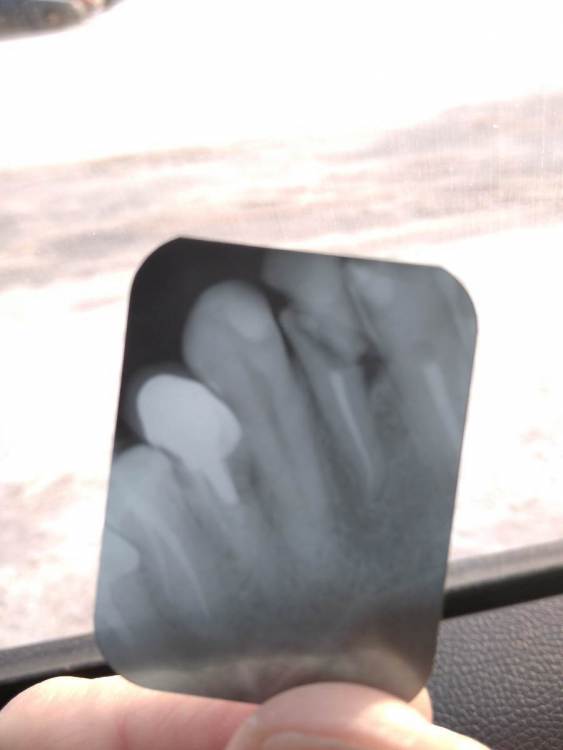

Pesok Опубликовано 12 января, 2022 Поделиться Опубликовано 12 января, 2022 Добрый день. Правая двойка сверху. У зуба аномальная подвижность. Сделал снимок - сломан корень. Был на консультации у двух врачей. Один говорит, что только полное удаление и имплантация. Другой говорит, что можно удалить верхнюю часть, а нижнюю - под коронку. Хотелось бы послушать мнение экспертов со стороны. Фото снимка прилагаю. Если не очень видно, постараюсь перефоткать более качественно. Спасибо Ссылка на комментарий

Bier Опубликовано 30 января, 2022 Поделиться Опубликовано 30 января, 2022 надо убрать отломок и оценить корень. На первый взгляд можно сохранить его. Ссылка на комментарий

Pavel-Pskov Опубликовано 31 января, 2022 Поделиться Опубликовано 31 января, 2022 Олег, есть ли смысл с таким карманом? Ссылка на комментарий